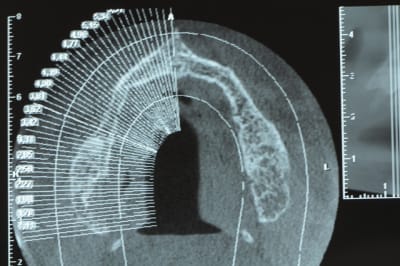

Ici le guide radio est préparé pour laisser passer l'embout de calage lors de la tomosynthèse de façon à ce que les deux appareils soient parfaitement stables.

les deux incisives centrales sont donc meulées.